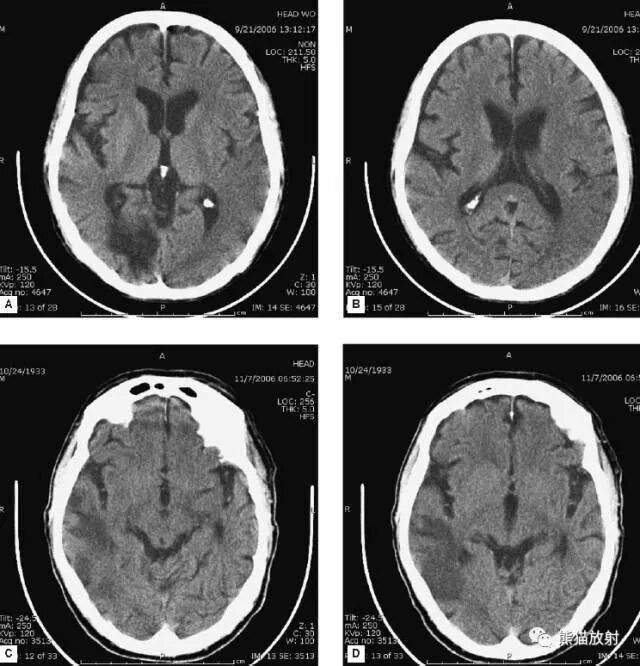

缺血性脑卒中

- 早期:脑水肿,灰白质分界模糊,脑沟消失;

- 中期:病变区域密度减低;

- 晚期:脑实质体积缩小。

A:陈旧性脑梗死,右枕叶体积缩小;

B:左枕叶急性脑梗死,灰白质分界模糊,脑沟消失;

另一患者:

C、D:亚急性期脑梗死,低密度,无明显占位效应。